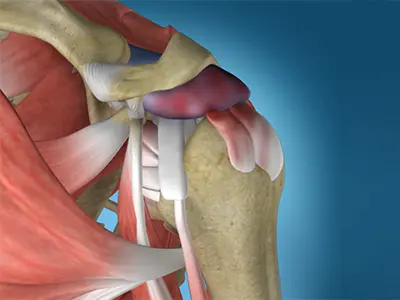

Shoulder Labrum Reconstruction

The labrum is a ring of fibrous cartilage surrounding the glenoid, which helps in stabilizing the shoulder joint.

Arthroscopic Bankart Repair

The labrum can sometimes tear during a shoulder injury. A specific type of labral tear that occurs when the shoulder dislocates is called a Bankart tear.

Shoulder Anterior Labral Repair

A shoulder anterior labral repair is a surgical procedure performed to address damage or injury to the anterior (front) labrum of the shoulder joint.

Posterior Shoulder Labral Repair

A posterior shoulder labral repair is a surgical procedure performed to address damage or injury to the posterior (back) labrum of the shoulder.